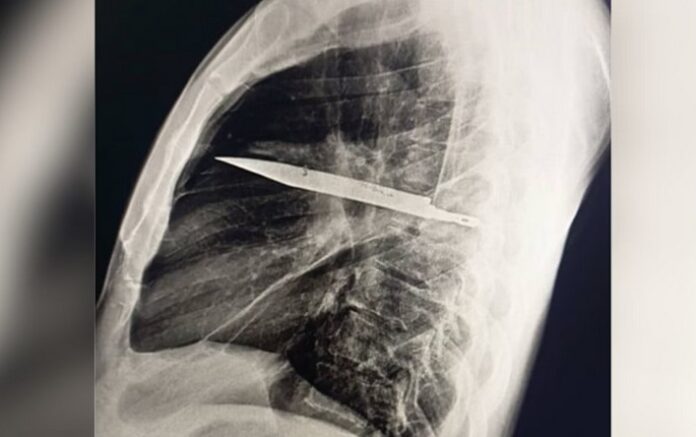

Já no hospital após oito anos, foram feitos exames radiológicos que revelaram uma lâmina alojada no lado direito do tórax, próxima à escápula, sem atingir órgãos vitais, mas no local havia secreção com pus, que foi atribuída à presença do corpo estranho e tecido danificado ao redor.